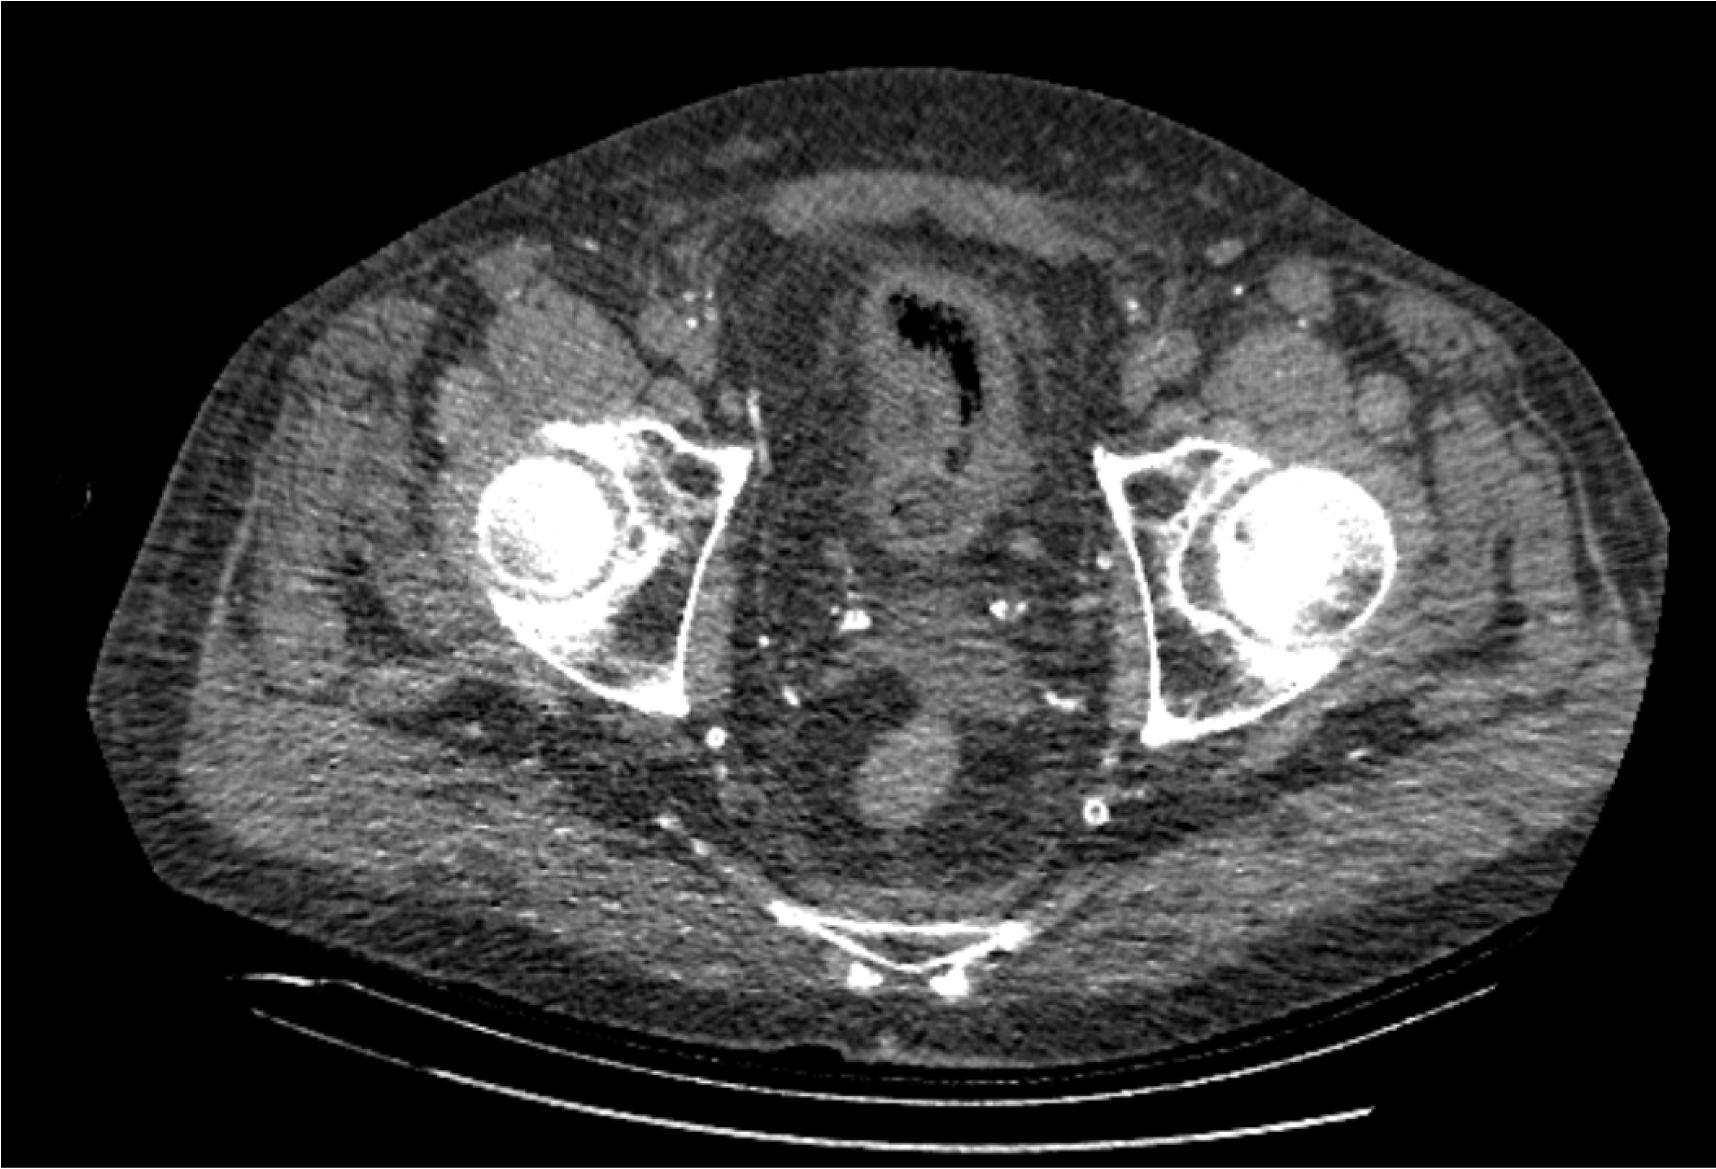

На следующий день состояние пациента оставалось тяжелым, с отрицательной динамикой, креатинин сыворотки возрос до 735,2 ммоль/л, Появились жалобы на слабость, тошноту. При осмотре: живот мягкий, вздут по всем отделам, при пальпации болезненный. Область почек не изменена, при пальпации безболезненна, патологических изменений в области почек не выявлено. Симптом поколачивания отрицательный билатерально. При УЗИ были обнаружены плевральный выпот по 300–400 мл с каждой стороны, гепатомегалия, увеличение размеров селезенки, асцит. Кроме того, в обеих почках были визуализированы тени, характерные для конкрементов. По данным компьютерной томографии (КТ) конкрементов не обнаружено, но в лоханке, на всем протяжении левого мочеточника и, частично, в правом мочеточнике, а также в мочевом пузыре визуализировался газ (рис. 1–6).

Рис. 4. Компьютерная томография органов брюшной полости, забрюшинного пространства, органов малого таза. Газ в почках

Рис. 5. Компьютерная томография органов брюшной полости, забрюшинного пространства, органов малого таза. Газ в левой почке